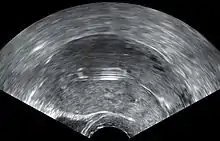

- Una "espiral perdida" ocurre cuando el hilo no puede ser sentido por una mujer en la revisión de rutina y no se ve en el examen con espéculo. Se pueden usar varios dispositivos colectores de hilo o pinzas simples para tratar de agarrar el dispositivo a través del cuello uterino. En los casos poco frecuentes en que esto no sea posible, se puede realizar una ecografía para verificar la posición de la espiral y excluir su perforación a través de la cavidad abdominal o su expulsión previa no reconocida.

El diu hormonal se inserta en un procedimiento similar al diu de cobre no hormonal, y solo puede ser insertado por un médico calificado. Antes de la inserción, se realiza un examen pélvico para examinar la forma y la posición del útero. También se recomienda que los pacientes sean examinados para detectar gonorrea y clamidia antes de la inserción, ya que una ITS en el momento de la inserción puede aumentar el riesgo de infección pélvica. Sin embargo, si una persona ha sido examinada previamente y no hay evidencia de infección en el examen, no es necesario retrasar la inserción del diu.[25]

Durante la inserción, la vagina se mantiene abierta con un espéculo, el mismo dispositivo que se usa durante la prueba de Papanicolaou. Se usa un instrumento de agarre para estabilizar el cuello uterino, se mide la longitud del útero para una inserción adecuada y se coloca el diu con un tubo angosto a través de la abertura del cuello uterino hacia el útero. Un tramo corto de monofilamento de plástico/nylon cuelga del cuello uterino hacia la vagina. La cuerda permite que los médicos y los pacientes verifiquen que el diu esté todavía en su lugar y permite una fácil extracción del dispositivo. Pueden ocurrir durante el procedimiento calambres de leves a moderados, que generalmente duran cinco minutos o menos. La inserción se puede realizar inmediatamente después del parto y después del aborto si no se ha producido una infección. El misoprostol no es efectivo para reducir el dolor en la inserción del diu.[26]